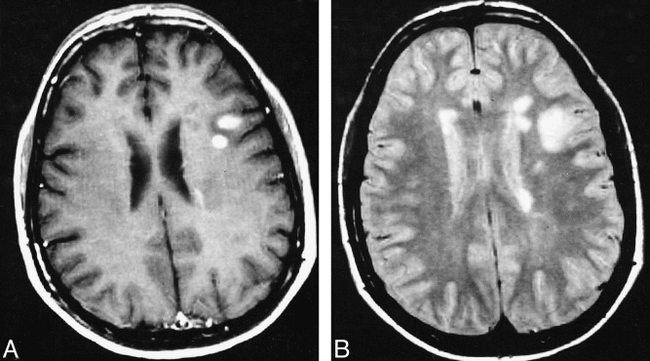

Fig 1. Axial brain MR images of a patient with CDMS, obtained before the onset of clinical symptoms. On the proton density–weighted image (A), many periventricular and discrete white matter lesions are visible. Two of them enhance on the contrast-enhanced T1-weighted image (B)